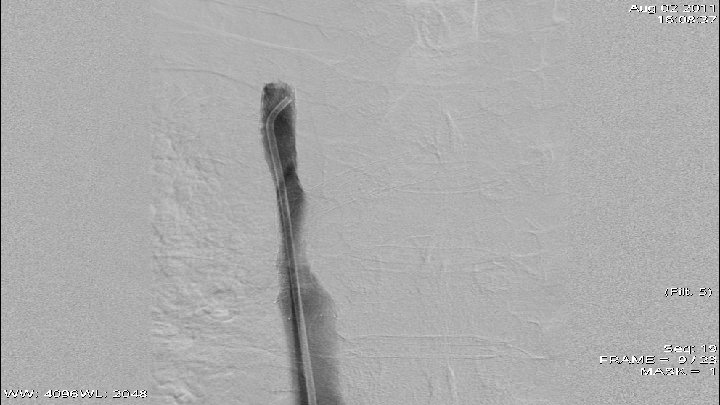

Case 1 q q q 66 y old patient May 2010 – small cell lung cancer was diagnosed April 2011 – venography - high grade stenosis of v. brachiocephalica billateral, PTA and stent implantation of v. brachiocephalica sinstra and baloon angioplasty of v. brachiocephalica dextra July 2011 – CT scan data for restenosis of v. brachiocephalica dextra August 2011 – venography - 90% restenosis of v. brachiocephalica dextra – after predilalatation was implanted stent.